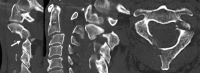

Fractures of the second cervical vertebra (C2, axis) are common in adult spine surgery. Those fractures occurring in younger adult patients are often associated with high-energy mechanism trauma, resulting in a "Hangman's Fracture." Management of these fractures is often successful with nonoperative means, though surgery may be needed in those fractures with greater displacement and injury to the C2-C3 disc. Older patients are more likely to sustain fractures of the odontoid process. The evidence supporting surgical management of these fractures is evolving, as there may be a mortality benefit to surgery. Regardless of treatment, longer-term mortality rates are high in this patient population, which should be discussed with the patient and family at the time of injury. Pediatric patients may suffer fractures of the axis, though differentiation of normal and pathologic findings is necessary and more difficult with the skeletally immature spine.